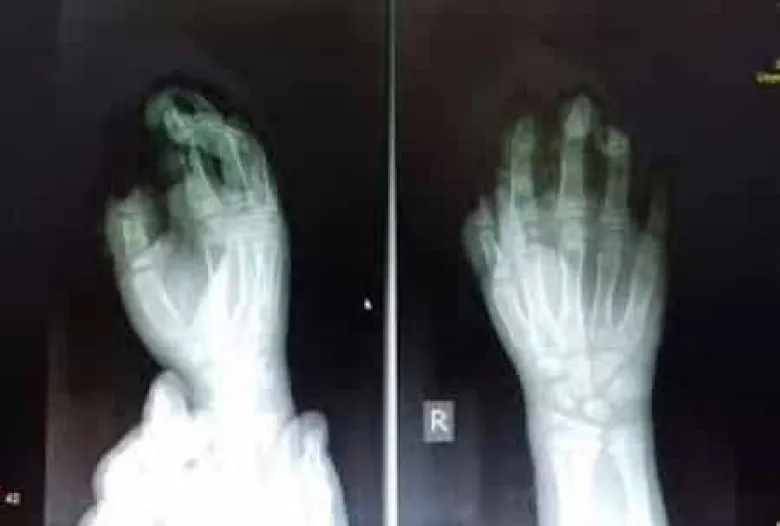

Պայթուցիկից տուժած երեխայի երկու մատը վերականգնվել է

«Երեխայի ձեռքի վիրահատությունը տևեց 3 ժամ և հաջողվեց վերականգնել առաջին և երրորդ մատները»,-հայտնում է «Սուրբ Աստվածամայր» ԲԿ-ի տնօրենը:

Պայթուցիկի հետեւանքով 2 մատները կորցրած 10-ամյա Գարուշ Թարվերդյանն այսօր` դեկտեմբերի 9-ին, դուրս է գրվել Երեւանի Սուրբ Աստվածամայր բժշկական կենտրոնից:

«Երեխան մեզ մոտ է տեղափոխվել բազմաթիվ կոտրվածքներով, մկանների ջնջխումներով, ձեռքի մեջ օտար մարմիններով և լուրջ տրավմատիկ վնասվածքներով: Վիրահատությունից հետո երեխայի ձեռքը կաշխատի, բացակայում է երկրորդ մատը, որը հետագայում հնարավոր կլինի վերականգնել»:

Հիշեցնենք, որ պայթուցիկի պայթյունի հետևանքով տղայի բութի ու ցուցամատի ծայրային ֆալանգները անդամահատվել էին, իսկ միջնամատը բժիշկներին հաջողվել էր պահպանել։ Տղան որոշել է` ոչ միայն ինքը այլևս չի գնելու պայթուցիկ, այլ նաև իր ընկերներին չի թողելու։